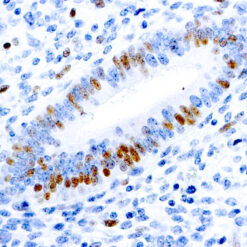

Iba1 (AIF1)

Actin-binding protein that enhances membrane ruffling and RAC activation. Enhances the actin-bundling activity of LCP1. Binds calcium. Plays a role in RAC signaling and in phagocytosis. AIF1 colocalizes with actin, and upon stimulation, translocates to lamellipodia. It is also a marker of human microglia and is expressed by macrophages in injured skeletal muscle. The gene encoding AIF1 resides in the tumor necrosis factor (TNF) cluster of genes, located in the region represented by the human major histocompatibility complex (MHC).

| Positive Control Tissue | Spleen |